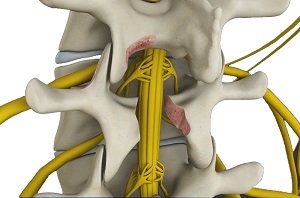

The spinal cord is protected by a bony column of vertebral bones, arranged one above the other. Injury or wear-and-tear can cause parts of the vertebrae to compress the nerves of the spinal cord, leading to pain, numbness or tingling in the part of the body that the nerve supplies.

Lumbar decompression is a surgical procedure performed to relieve pressure over the compressed nerves in the lower spine (lumbar region).

- The lamina (bony arch of your vertebra) may be removed (laminectomy) and the facet joints may be trimmed to reach the compressed nerve.

- Your surgeon removes any bone spurs or disc material that is pressing on the spinal nerve.